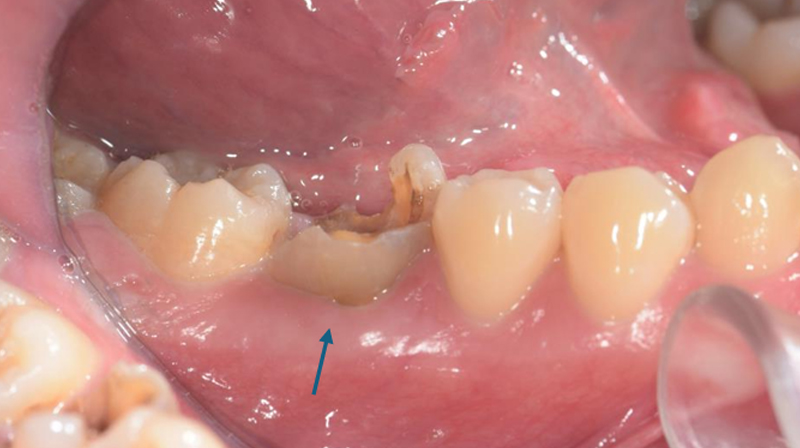

術前評估口腔狀況

右下第一大臼齒斷裂